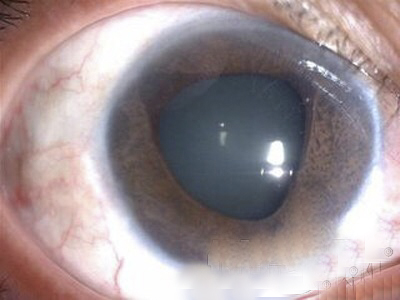

A:飛蠅症又稱飛蚊症和玻璃體混濁,是指玻璃體內出現不透明體,造成患者視物出現模糊。人出生時玻璃體呈凝膠狀態,是重要的屈光介質,正常的玻璃體隨著年齡逐漸出現液化,從而導致玻璃體混濁。此外,一切玻璃體混濁是由於病理原因所導致,例如玻璃體出血、葡萄……

A:眼前出現飛蚊的症狀往往是因為玻璃體發生了液化、變性和混濁,通常情況下玻璃體的混濁,比較多見於近視眼的人和年歲比較大的中老年人,還要特別重視的一個問題是當眼底有病變發生的時候,也會出現玻璃體的混濁、玻璃體混濁的加重,這時候眼前飛蚊的症狀需要做……

A:眼睛裡有飛蚊的現象主要是因為玻璃體發生了液化、變性和混濁,玻璃體原本在眼睛裡邊是一個膠凍狀的結構,由於近視眼以及中高度近視或者年齡過大了,中老年人就會出現玻璃體的液化、變性和混濁,這種情況下很難通過任何治療,將已經液化的玻璃體恢復到膠凍狀的……